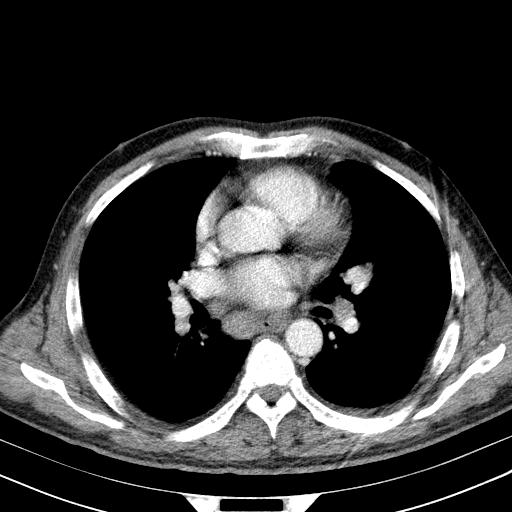

先行ct平扫,纵膈内多发软组织影,ct值约为36hu,以下为增强扫描和腹部平扫。

经典?纵膈多发肿大淋巴结。腹膜后未见异常。

淋巴瘤?胸腺瘤?

1)考虑淋巴瘤。2)双侧少量胸腔积液。